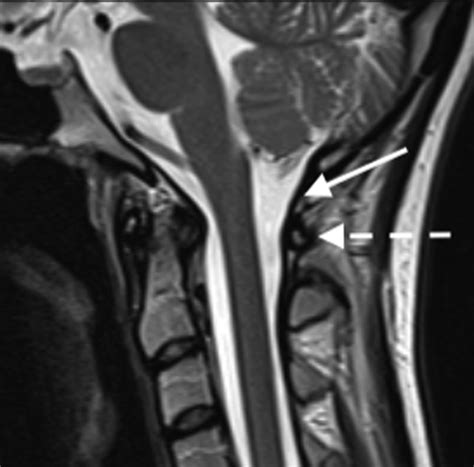

Cervical Spondylosis

Cervical spondylosis is a degenerative condition of the cervical spine, often caused by aging or wear and tear. It can lead to stiffness, pain, and reduced neck suppleness. To manage cervical spondylosis:

• Consult a healthcare professional for a proper diagnosis and treatment plan.

• Perform regular neck exercises and stretches.

• Maintain good posture and avoid activities that strain the neck.